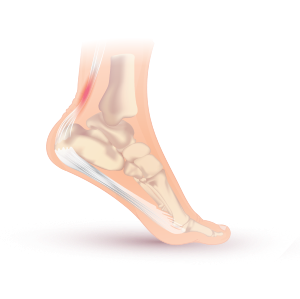

صورة تشريحية لوتر أخيل: الوتر المصاب باللون الأحمر.